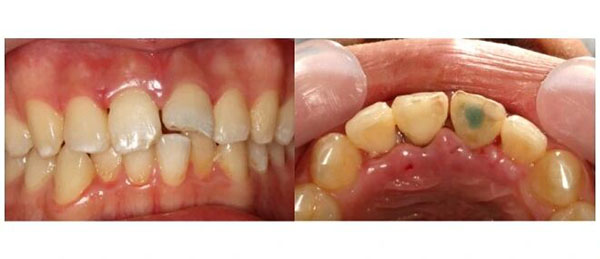

术后1年,复查,牙齿稳稳的。

术后2年,再来,还是好好的。

术后4年,他来复查,已经是个高高瘦瘦的大学生了。

他已经大学毕业,参加了工作。复查的结果依然是:牙齿稳固,牙周健康。

这8年,那颗曾经差点被拔掉的牙齿,和他一起度过了整个青春,从来没有成为他的困扰。他照常吃饭,照常笑,照常参加面试,照常走进人生的每一个新阶段。